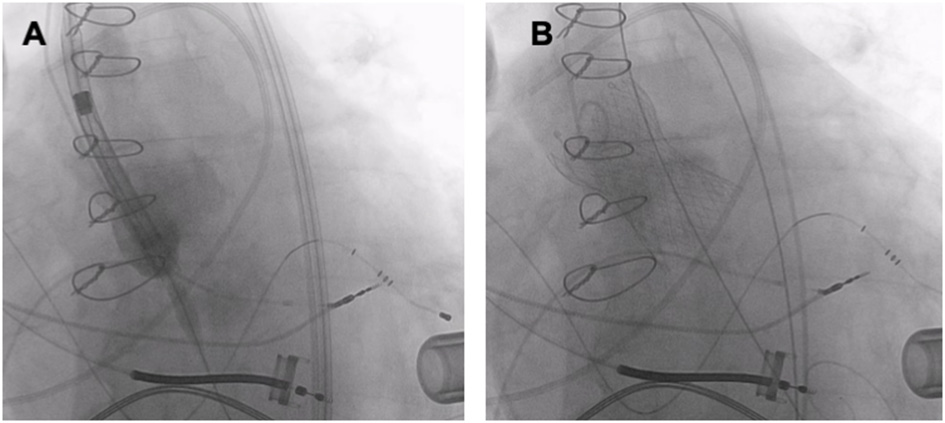

Figure 5

TAVR (Medtronic Evolut R 34 mm) in a patient with pure AR and a left ventricular assist device. (A) THV deployment. (B) Fluoroscopy after TAVR.